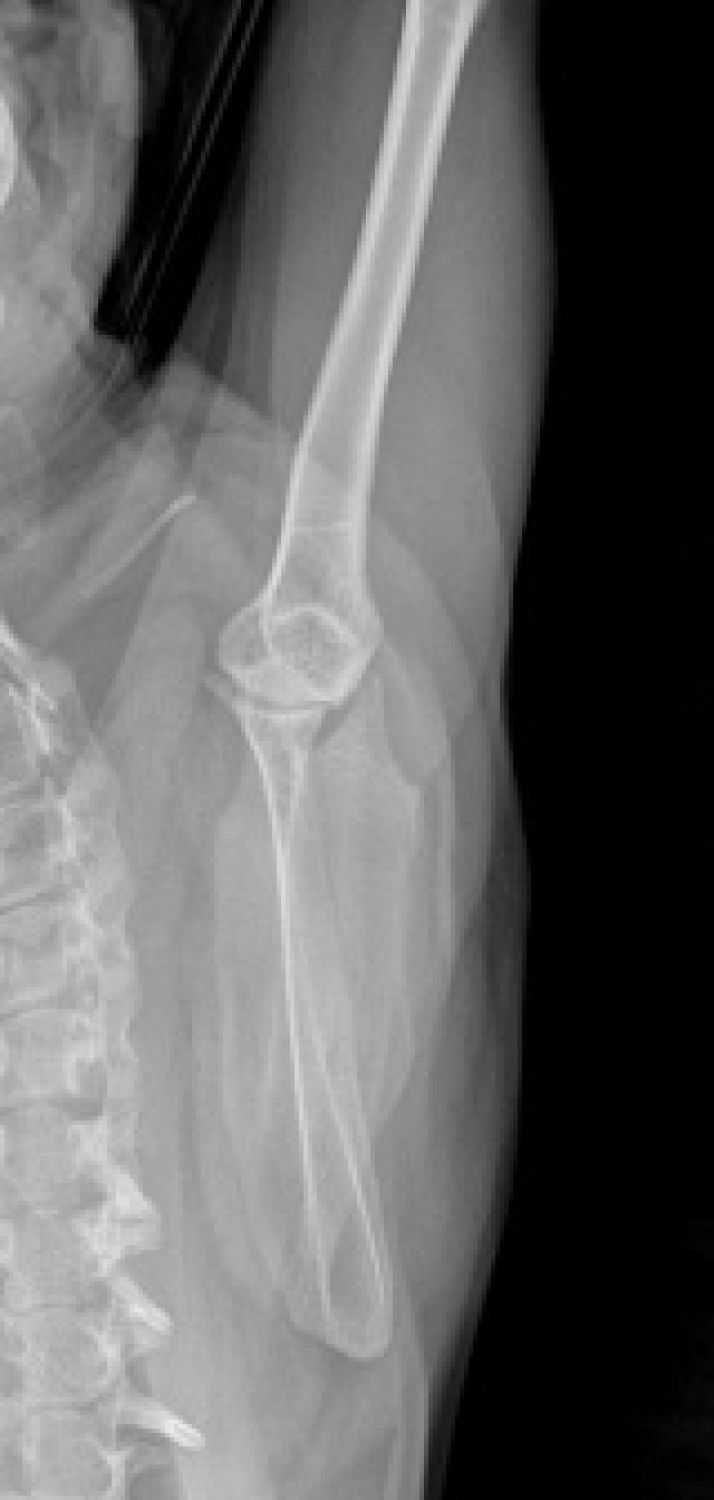

Humerus

Atlas Pozitionari